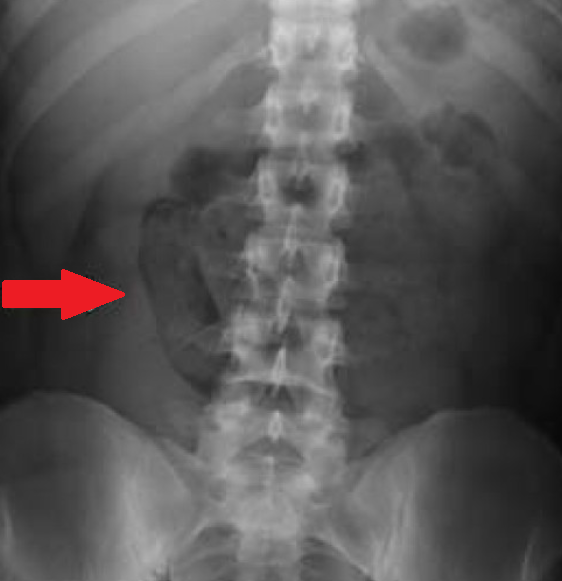

Διάταση αριστερού ουρητήρα λόγω παρουσίας πιθανής εμφύτευσης (Ευγενική παραχώρηση Dr. V. Penopoulos)